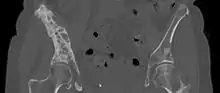

CT scan in the coronal plane of bone metastases of the hip bone, in a 60-year-old woman with parotid gland cancer. The more affected side is very irregular and sclerotic (visible as brighter in this presentation).